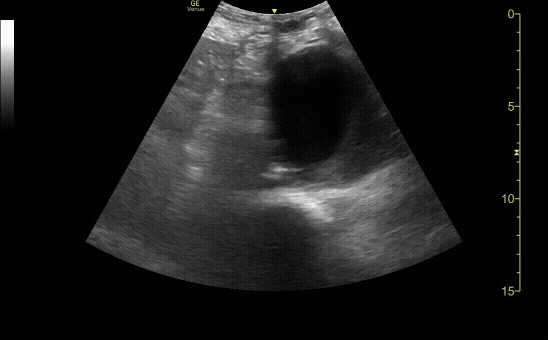

Abdominal Aortic Aneurysm that measured 8cm in size.

c/o Ginny Kim, MD